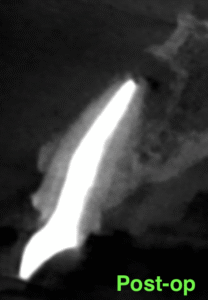

さておき、根充+支台築造後にPA, CBCTを撮影した。

#7

#10